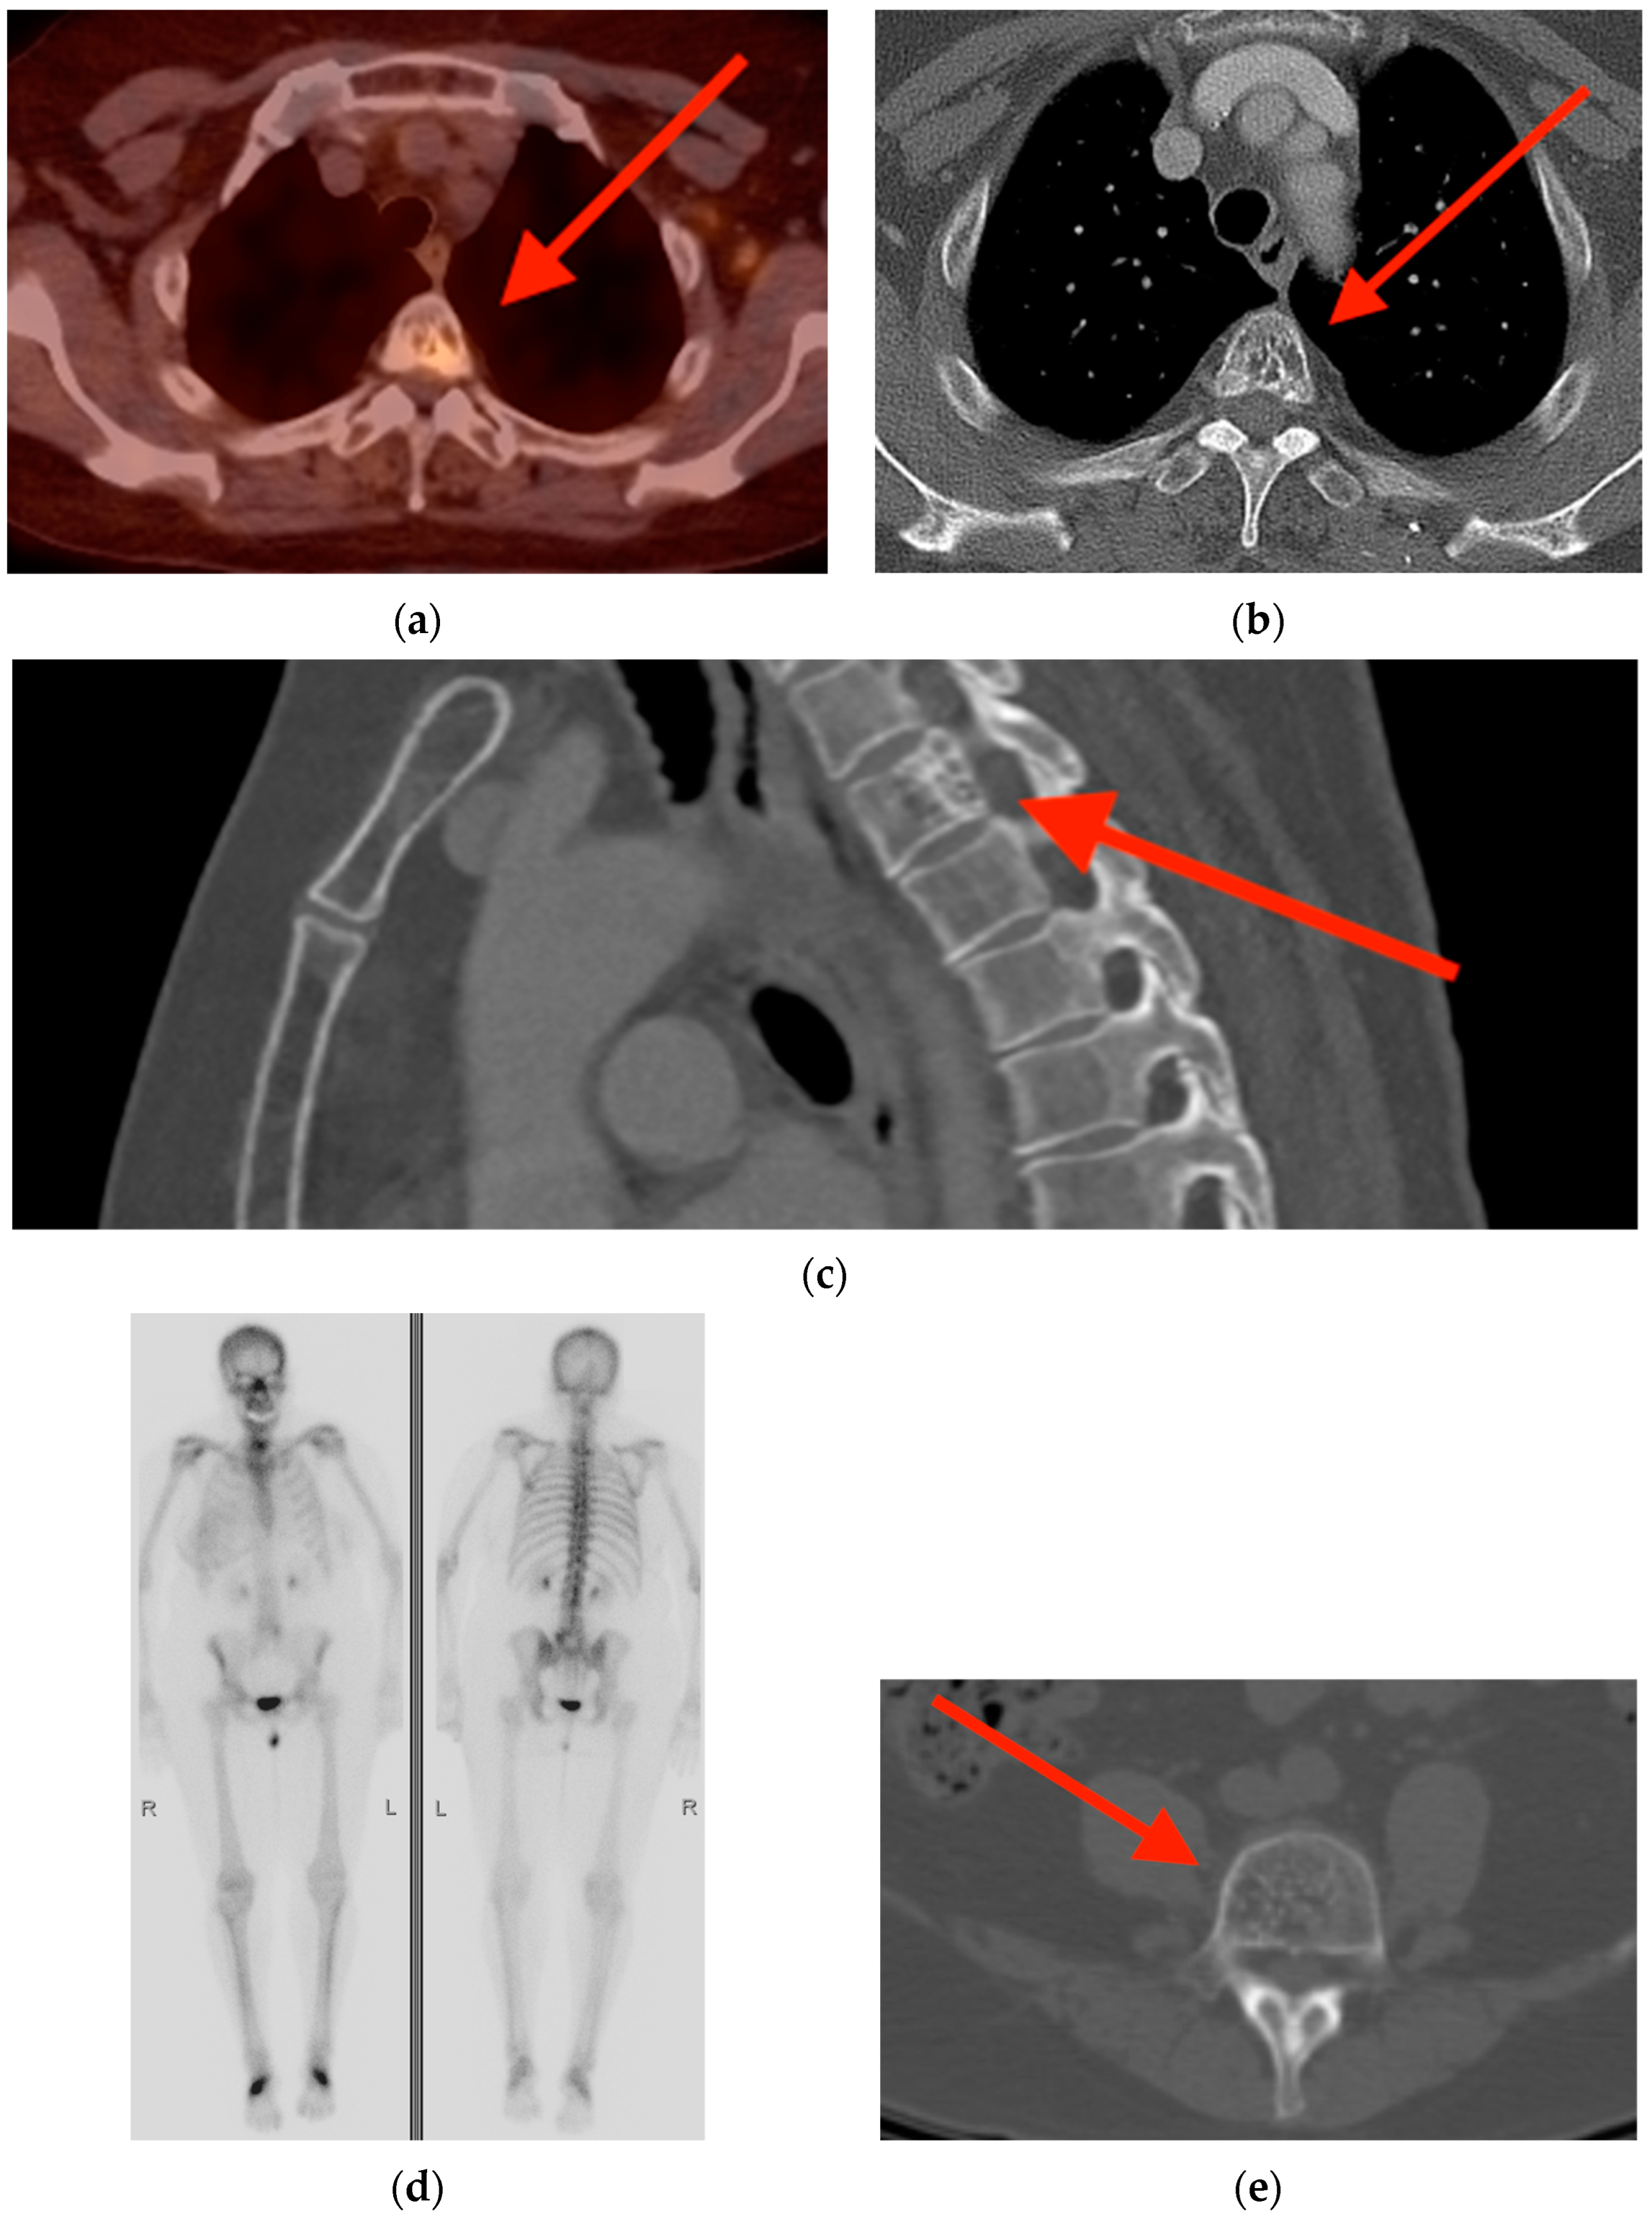

2.3. Enchondroma

- Mulligan, M.E. How to Diagnose Enchondroma, Bone Infarct, and Chondrosarcoma. Curr. Probl. Diagn. Radiol. 2019, 48, 262–273. [Google Scholar] [CrossRef] [PubMed]

- Cheung, H.; Yechoor, A.; Behnia, F.; Abadi, A.B.; Khodarahmi, I.; Soltanolkotabi, M.; Shafiei, M.; Chalian, M. Common Skeletal Neoplasms and Nonneoplastic Lesions at 18F-FDG PET/CT. Radiographics 2022, 42, 250–267. [Google Scholar] [CrossRef]

- Crim, J.; Schmidt, R.; Layfield, L.; Hanrahan, C.; Manaster, B.J. Can imaging criteria distinguish enchondroma from grade 1 chondrosarcoma? Eur. J. Radiol. 2015, 84, 2222–2230. [Google Scholar] [CrossRef]

- Subhawong, T.K.; Winn, A.; Shemesh, S.S.; Pretell-Mazzini, J. F-18 FDG PET differentiation of benign from malignant chondroid neoplasms: A systematic review of the literature. Skelet. Radiol. 2017, 46, 1233–1239. [Google Scholar] [CrossRef]